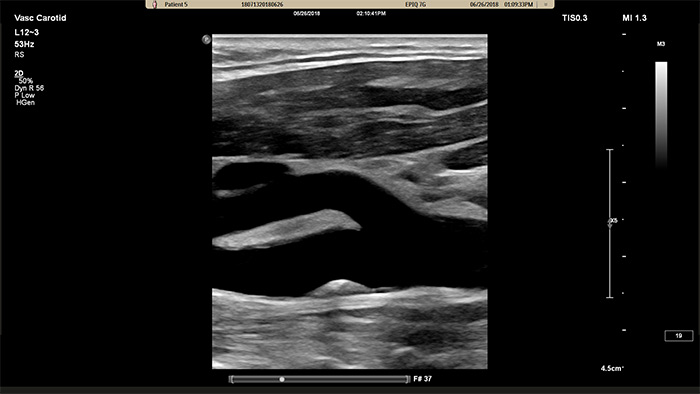

Der neue XL14-3 xMATRIX Schallkopf hat beeindruckende 56.000 Elemente, die alle mit einem separaten Mikrokanal verbunden sind. Der XL14-3 Schallkopf ermöglicht mit seiner mehrdimensionalen elektronischen Fokussierung die Bildgebung von Gefäßanatomien und Plaquemorphologien in hauchdünnen Schichten. Wichtigster Vorteil: die außergewöhnliche Diagnosesicherheit bei der Beurteilung von Stenosen und gefährlicher Plaque.